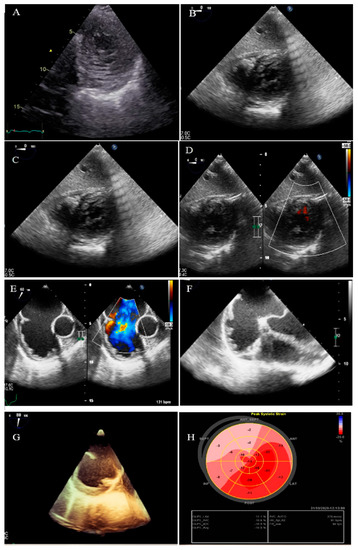

2.4. Case #4. Biventricular Non-Compaction (BVNC) with Ostium Primum Atrial Septal Defect (ASD) Plus Complete Heart Block

A 34-year-old lady, 34 weeks pregnant, was referred to the hospital with dyspnea, worsening over the course of the last week. A total of 2 h after admission, she experienced sudden cardiac arrest and was successfully resuscitated. At that time, the ECG monitoring was in favor of torsade de pointes. During the hospital course, intermittent complete heart block was noted. She did not report any CVD symptoms before this. Her first pregnancy was uneventful, and her healthy boy was 3 years old. TTE and TEE revealed non-compaction of the left and right ventricles, mild biventricular systolic dysfunction (global LVEF = 40%, tricuspid annular plane systolic excursion = 14 mm, and RV Sm = 8 mm), a large ostium primum ASD (34 mm), and moderate pulmonary hypertension with the pulmonary flow to systemic flow ratio (QP/QS) of 2.1 (Figure 4). During the 4-week follow-up, she developed a couple of symptomatic ventricular tachycardia, which properly resumed to a normal rhythm by electrical cardioversions. Finally, the heart team decided to schedule her for a cesarean section with temporary pacemaker backup. After the delivery of a living, healthy baby, she refused cardiac surgery. Therefore, based on the patient’s and her family’s request, she underwent implantation of a single chamber implantable cardioverter-defibrillator (ICD). During the 4-month follow-up, it did not record a high ventricular rate.

Figure 4.

Two-dimensional transthoracic echocardiographic views of case #4, (A); Biventricular apical SAX view, (B,C); Transesophageal gastric views, illustrating hypertrabeculated apical portions in addition to deep intertrabecular recesses. (D); Color Doppler echocardiography, showing evidence of direct blood flow from the ventricular cavity into deep intertrabecular recesses. (E–G); Two- and three-dimensional mid-transesophageal echocardiographic views, showing a large ostium primum type of atrial septal defect with left to right shunt. (H); Speckle tracking echocardiographic findings, compatible with myocardial performance impairment, mild in apical to severe in basal segments, and GLS = −10.9%. (I–L); Twelve-lead electrocardiography and a couple of tracings at different times, showing complete heart block and sustained runs of wide QRS tachycardia.